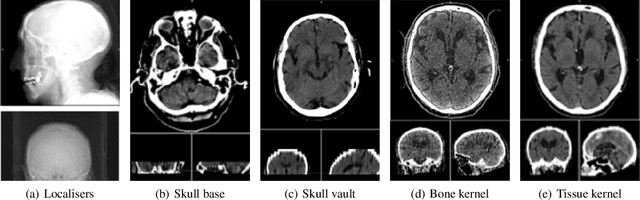

Abstract:Despite the large amount of brain CT data generated in clinical practice, the availability of CT datasets for deep learning (DL) research is currently limited. Furthermore, the data can be insufficiently or improperly prepared for machine learning and thus lead to spurious and irreproducible analyses. This lack of access to comprehensive and diverse datasets poses a significant challenge for the development of DL algorithms. In this work, we propose a complete semi-automatic pipeline to address the challenges of preparing a clinical brain CT dataset for DL analysis and describe the process of standardising this heterogeneous dataset. Challenges include handling image sets with different orientations (axial, sagittal, coronal), different image types (to view soft tissues or bones) and dimensions, and removing redundant background. The final pipeline was able to process 5,868/10,659 (45%) CT image datasets. Reasons for rejection include non-axial data (n=1,920), bone reformats (n=687), separated skull base/vault images (n=1,226), and registration failures (n=465). Further format adjustments, including image cropping, resizing and scaling are also needed for DL processing. Of the axial scans that were not localisers, bone reformats or split brains, 5,868/6,333 (93%) were accepted, while the remaining 465 failed the registration process. Appropriate preparation of medical imaging datasets for DL is a costly and time-intensive process.